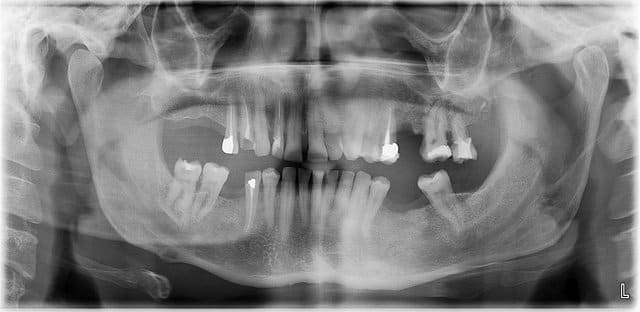

Je reçois un patient fumeur (1 pqt/j) pour la 1ere fois

il me dit avoir mal (tu m’étonnes !! )au site d'extraction (26) réalisée il y a 4 mois ....

après radio et photo je ne sais quelle conduite adopter ?

C'est l'os qu'on voit en marron? Parce que ca sent le séquestre dans ce cas

C'est effectivement de l'os

Que faire ou où envoyer ?